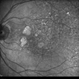

- geographic atrophy

- AMD, geographic atrophy